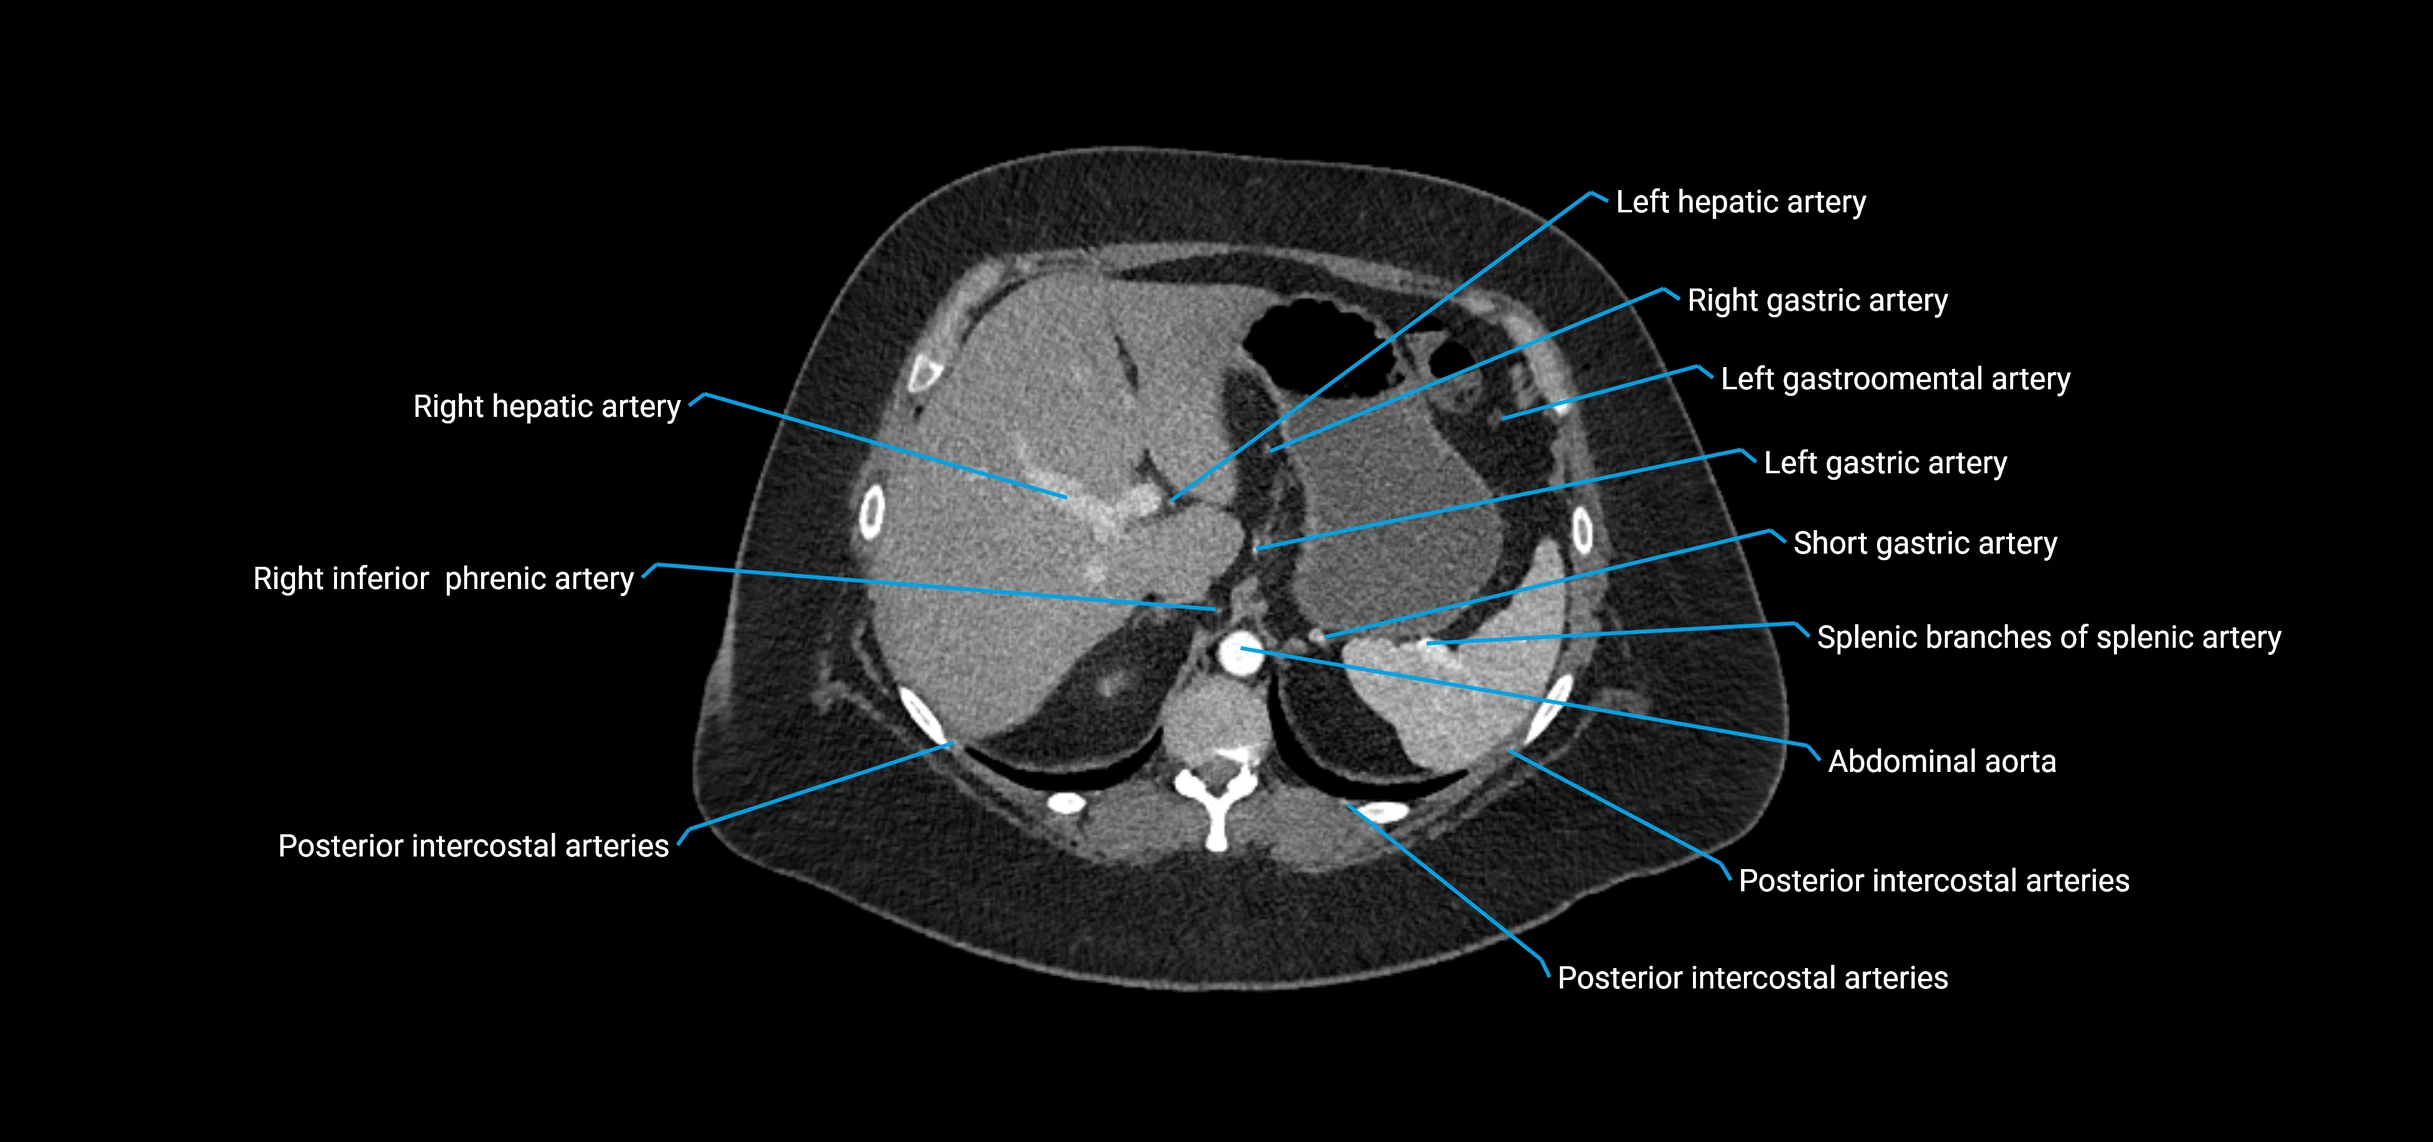

CT images

image

Contrast-enhanced CT (CTA):

• Gold standard for abdominal aortic imaging

• Provides excellent detail of lumen, wall, aneurysm, thrombus, and branch vessels

• Multiplanar and 3D reconstructions help in aneurysm measurement, stent graft planning, and dissection evaluation